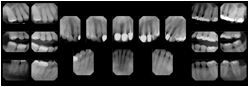

- OO-1. Intra-oral Full Mouth Series Structured Display